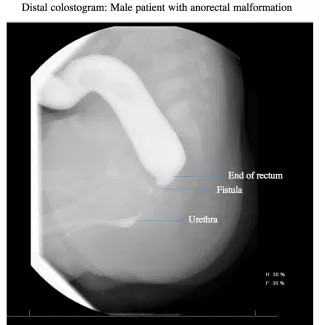

Distal colostogram: male patient with anorectal malformation

Before the second operation, where an anal opening will be made in the correct location, within the anal sphincter, your child may need to have a radiographic study called a distal colostogram to help prepare for surgery. The study helps to determine the distance from the blind end of the rectum to the skin and if there is a fistula.

If a fistula is found to the urogenital system, it will be closed at the time of the second operation. The stoma will be left intact, and not closed, to allow the new anus to heal. After this operation, the baby can go home to recover.